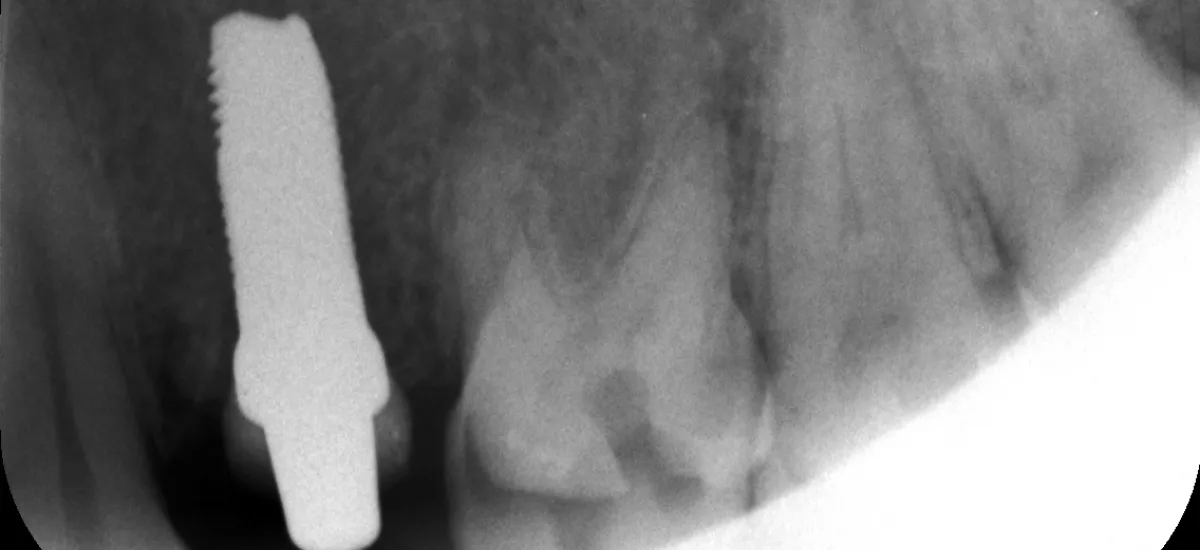

• Les implants en céramique d'oxyde de zirconium, dits implants zircone, font partie des plus récentes innovations de l'implantologie moderne.

• Le recul clinique est parfait et le taux de succès est semblable par rapport aux implants en titane.

• Publication des cas cliniques :